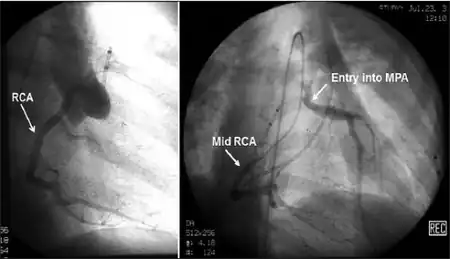

| Possible communication between left coronary artery and pulmonary artery in a 45-year-old woman with Bland-White-Garland syndrome. | |

Historically ALCAPA was diagnosed with conventional angiography. Today echocardiography is easily used. It can provide direct visualisation of the anomalous coronary artery and other associated structural abnormalities, and it can also assess myocardial function .The use of pulse and color-flow doppler can sometimes visualise reversal flow in the pulmonic artery. Other non-invasive methods used are computed tomography (CT) as well as magnetic resonance imaging (MRI) which enable a direct visualisation of the arteries as well as the myocardial viability.[3]